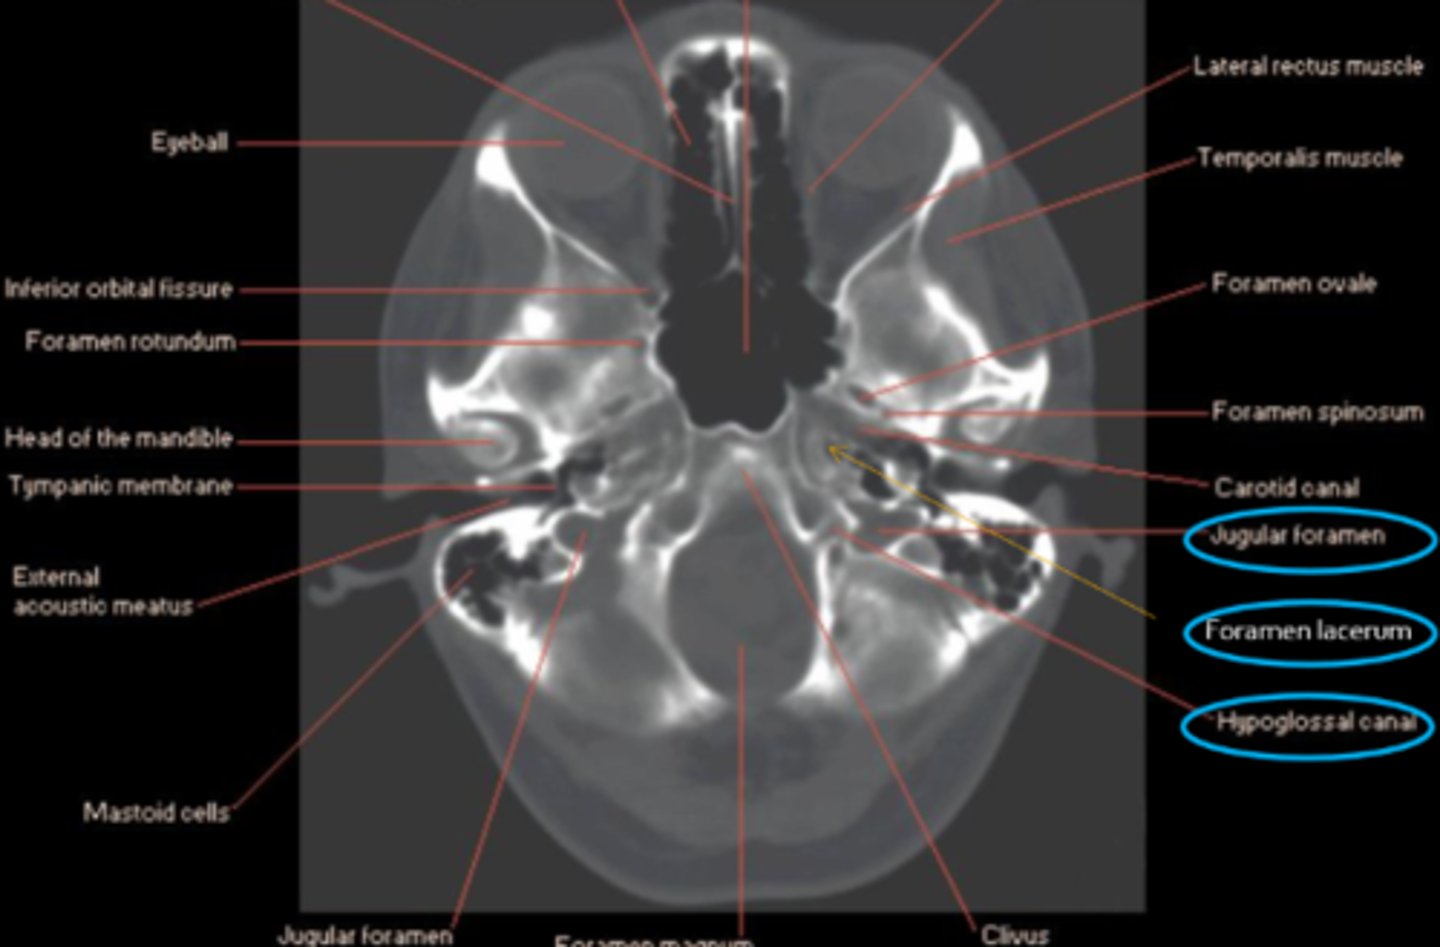

What 3 anatomical locations are targeted in Vernet's syndrome?

jugular foramen = CN IX, X, XI

foramen lacerum = ICA, symp fibers

hypoglossal canal = CN XII